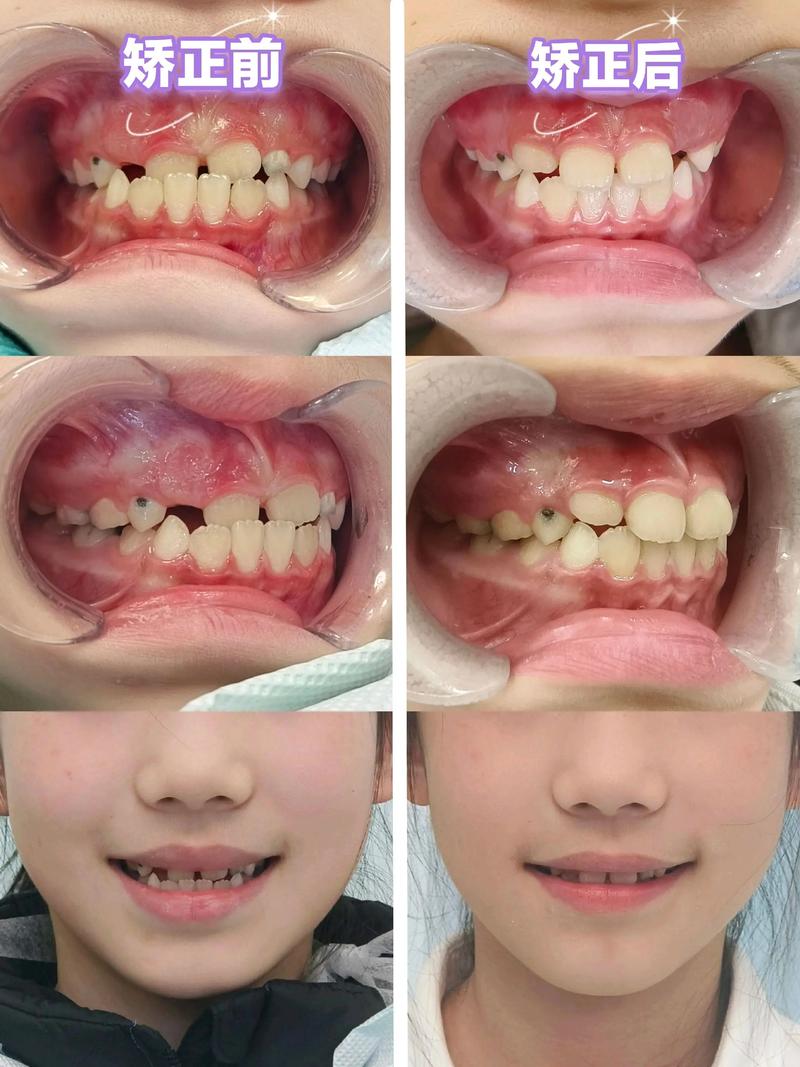

A:可从以下方面判断:①是否有口腔正畸学专科培训背景(如硕士、博士学历或专科进修经历);②是否能详细解释治疗方案、预期效果及风险;③是否要求拍摄全面影像学检查(如头颅侧位片、CBCT);④案例是否真实可查(如治疗前后的对比照片);⑤沟通是否耐心,是否尊重患者意见。